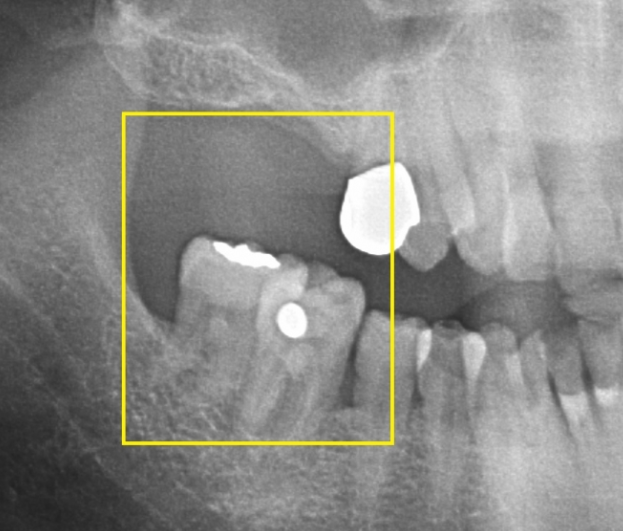

치아가 빠져 빈 공간이 생기게 되면 빠진 치아의 옆 치아 혹은 위아래로 맞닿는 치아가 그 빈 공간으로 이동하게 돼 치열이 망가지게 되면 틈이 생기고 음식물이 끼기 시작합니다. 음식물이 자주 끼게 되고 관리마저 잘되지 않으면 붓고 통증이 생깁니다.

백연화 교수는 "빈 공간을 지속적으로 방치하면 음식물을 씹는 것이 어렵게 돼, 소화 장애나 영양 부족 등 각종 전신적인 합병증을 유발할 수 있다"라며, "한 두 개의 치아가 빠져 지금 당장 불편감이 없다고 방치한다면 향후 치료를 받고자 할 때 추가적인 교정이나 보철치료 외에도 심한 경우 치아를 모두 발치해야 할 수도 있다"라고 전했습니다.

이어 백 교수는 "치료의 적기를 놓치면 멀쩡한 치아에 하지 않아도 됐을 치료를 하게 돼, 훨씬 더 큰 비용과 시간이 소요될 수 있고, 치료 결과도 좋지 않을 가능성이 높다"라며, "치아가 망가졌다면 가능한 한 빨리 치과 방문 후 적절한 치료를 받는 것이 필요하다"라고 조언했다고 합니다. 치아가 빠진 자리를 수복하는 방법에는 브릿지, 틀니 그리고 임플란트 등이 있습니다. 치아가 빠진 위치나 골상태, 주변 치아 상태 등에 따라 선택하게 되는 치료 방법은 달라집니다.